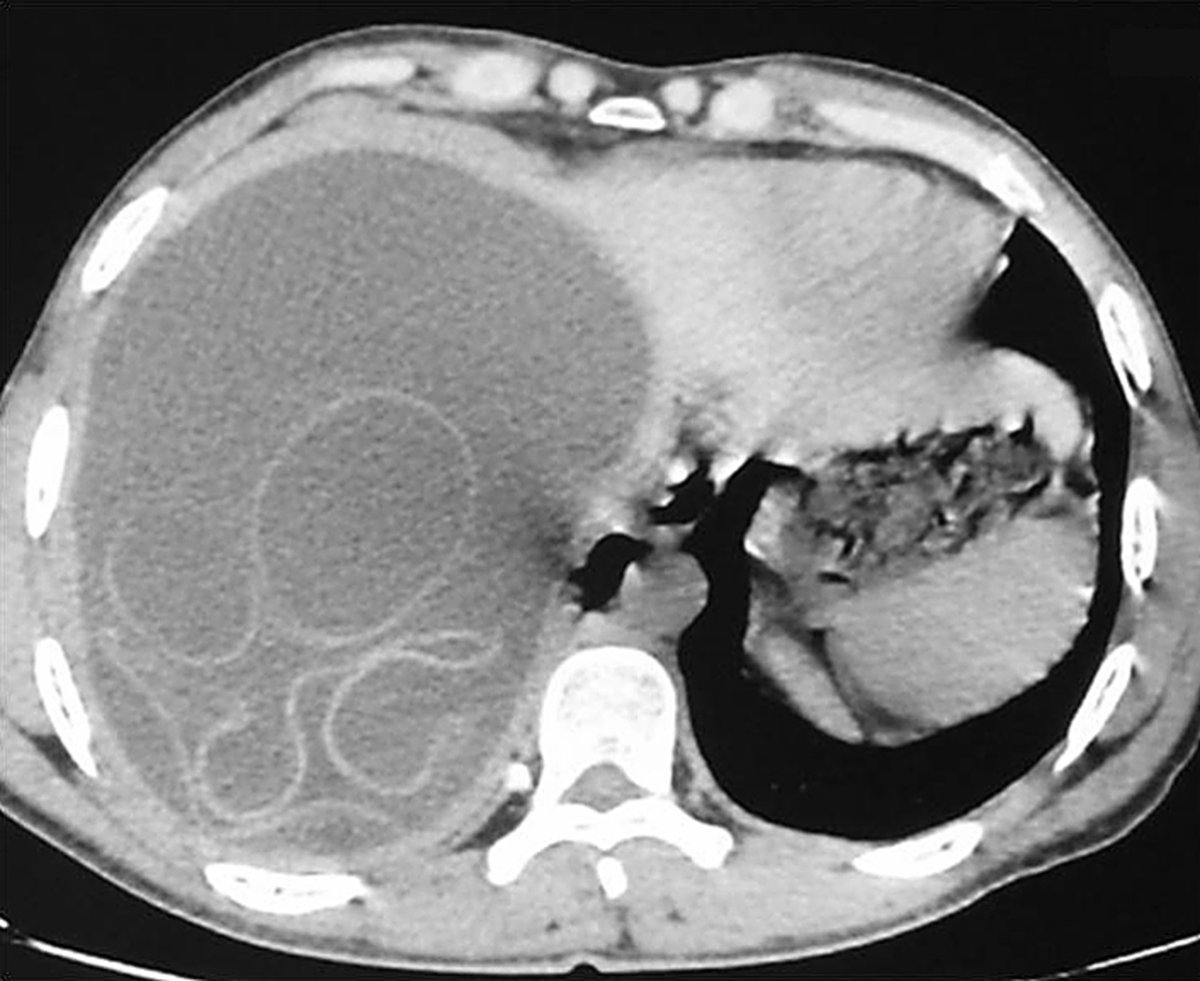

A 30 y/o man with a 15-month history of intermittent discomfort in the right upper quadrant of the abdomen. The physical examination revealed hepatomegaly with a palpable hepatic mass. - What is the diagnosis ? #medtwitter #foamed #usmle

22

34

238